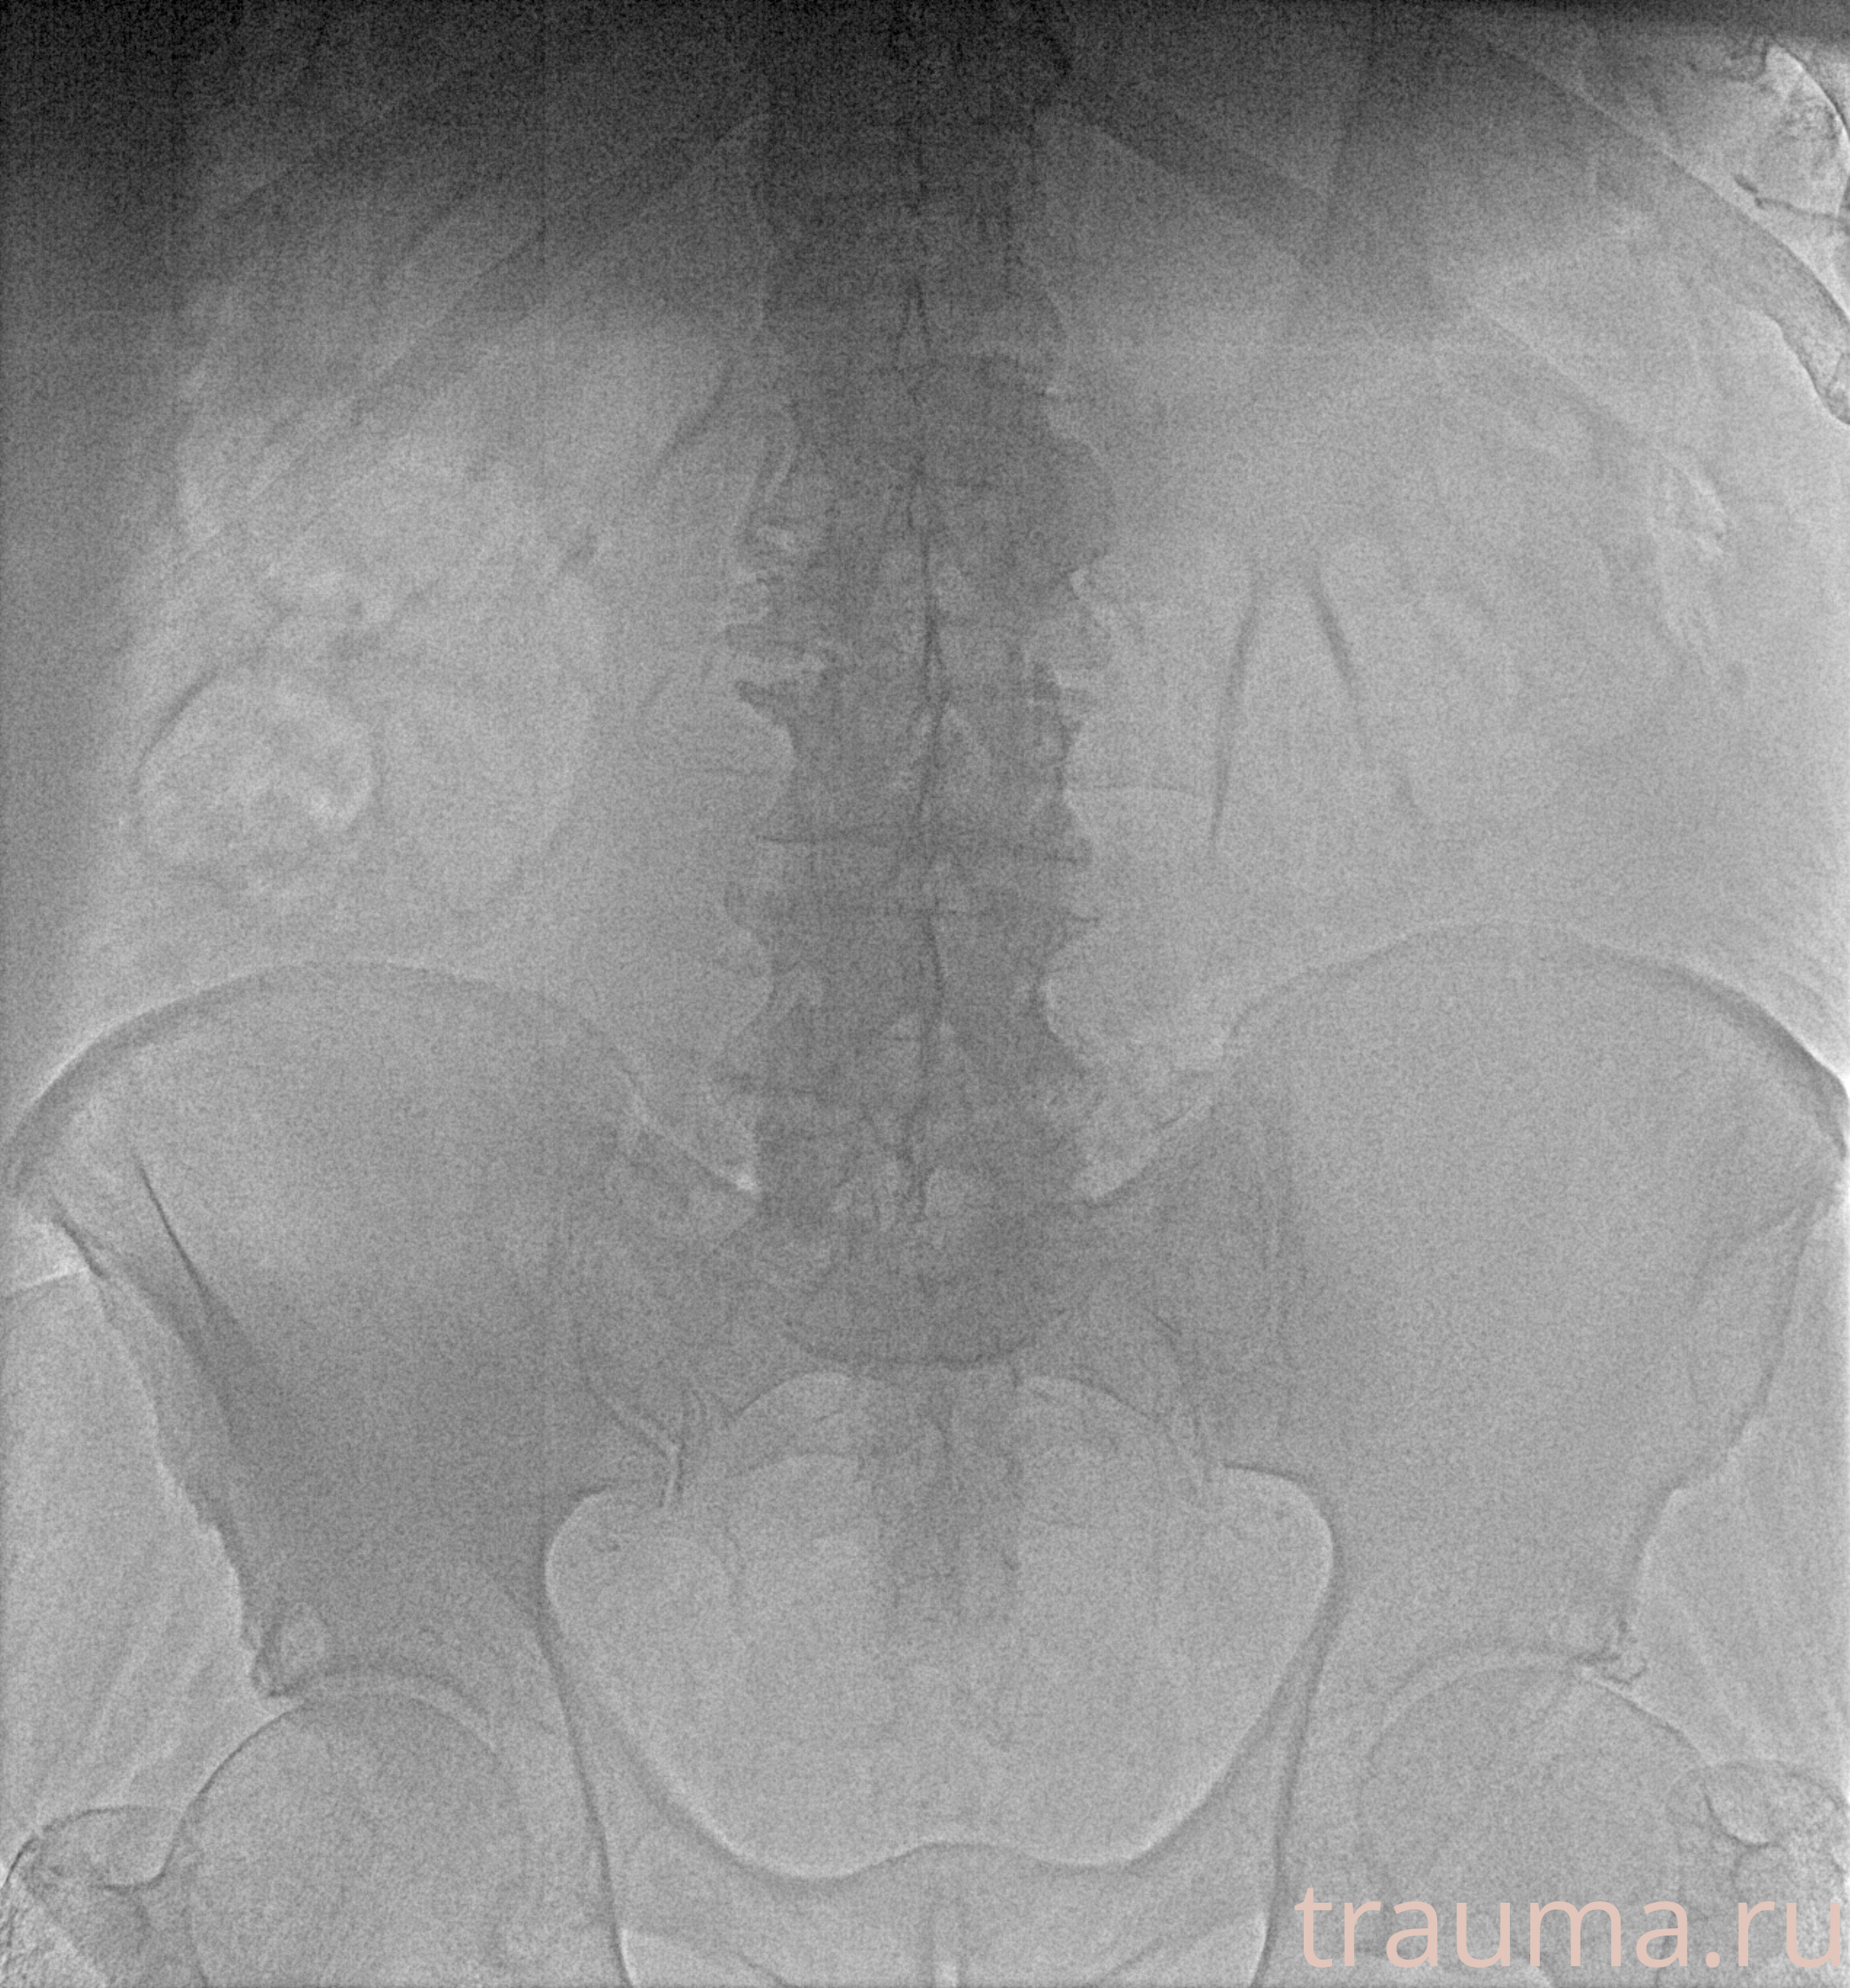

Рентген на дому: по вашему адресу приезжает врач-рентгенолог, травматолог-ортопед с мобильным рентгеновским аппаратом, проводит диагностику травмы или заболевания, делает необходимые рентгенограммы, дает рекомендации по дальнейшему лечению. Получить качественные снимки в домашних условиях возможно благодаря уникальной методике, разработанной МосРентген Центром для института  Склифосовского